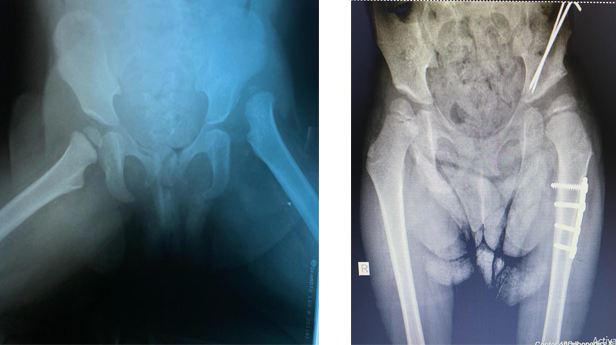

خلل التنسُّج الوركي ما بين الأطفال والمراهقين

يمكن لطبيب الأطفال اكتشاف مرض خلل التنسُّج الوركي، أو تشخيصه بتصوير الألتراساوند (تصوير فوق صوتي)، وذلك في حالة ولادة الطفل بالوضع المقعدي. ويتولى فريقنا علاج الأطفال المصابين بهذا الخلل بالوسائل غير الجراحية، إلى جانب الإجراءات الجراحية إذا لزم الأمر.